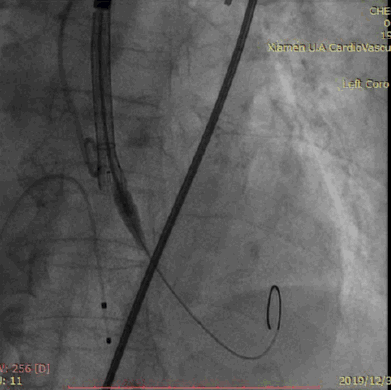

TAV8-1722球囊扩张